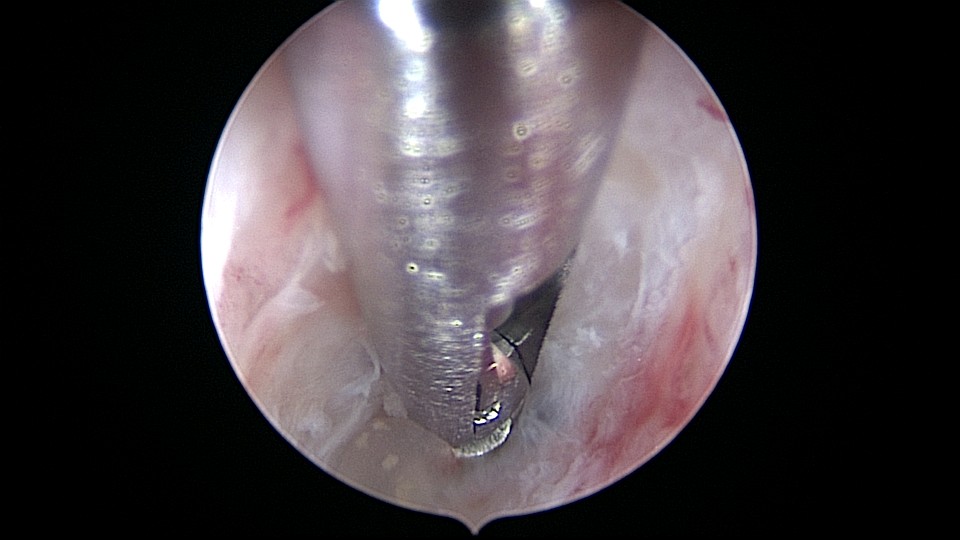

患者58岁,G2P1,顺产1次。安环35年,绝经15年,5年前在外院取环失败。术前B超提示子宫后位,O型环嵌顿,环顶端距宫底0.7cm。宫腔镜术中见阴道口狭小,无法置入窥阴器,宫颈外口狭窄,镜鞘缓慢扩大。宫颈内口粘连,左侧似有一小孔,异物钳扩大小孔,见较多浓稠黄色液体流出,冲洗干净后推进宫腔镜,见2个O型节育环,上面的环取出顺利,下面那个环与宫腔侧壁嵌顿,2次牵拉滑脱,第三次一张一驰松动节育环,再缓慢拉出,宫底见2道环压痕。